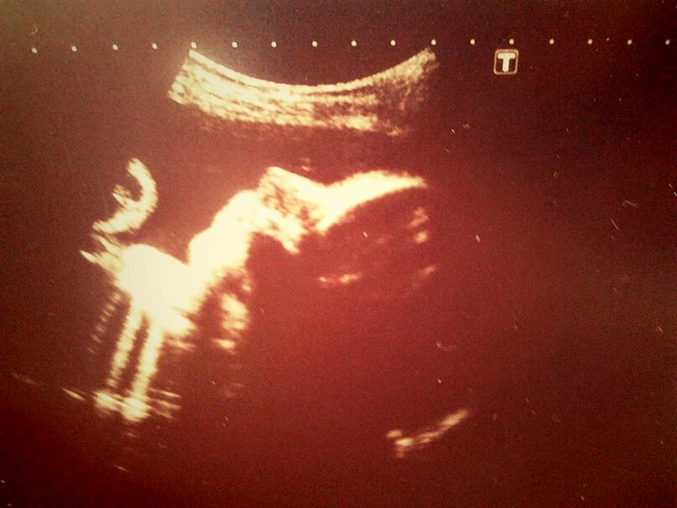

Доча лежит правильно, на УЗИ вчера врачу разрешила все измерять вдоль и в поперек:-) Моя прибавка составляет 7,5 кг, а доча весит уже 1700 кг:-) Вооружилась я бандажем уже, так как пуз стал тяжелым, а так же прикупили плед на выписку:-) Сегодня в блокнот переписала все свои списки, что нужно докупить. Так как скоро едим в Херсон и там первый месяц не будет интернета:-) Вообщем еще немножечко осталось, 30.05 пойдем к врачу и открепимся от этой ЖК, чтоб потом встать на учет в Херсоне:-) Написала все сумбурно, но вроде ничего не забыла :-)